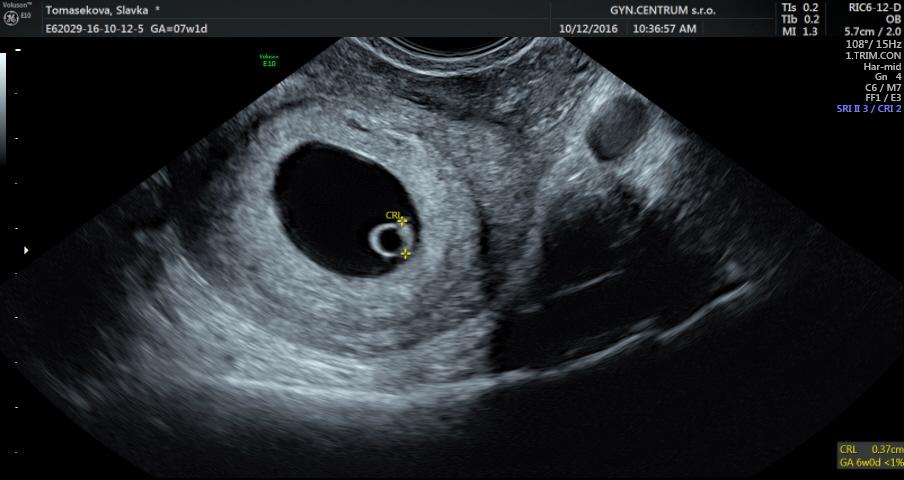

Ahojky kocky tak prva kontrola dopadla na vybornu videli a aj poculi nase drobatko... ovulka bola posunuta a tak nase drobatko je cca o 5 dni mensie.. o 2 tt kontrola 😃

Jeeeeeej, jake zlateeee. Gratulujem 🙂 kolko meria. Lebo vidim ze merane je telicko. Takisto aj u mna bolo. Niekto meria od hlavicky......

@alexandraala v právo dole 0,37 a 6+0 tt

@emakiki

@alexandraala ano presne tak... ovu bola oneskorena cca 4-5 dni ...